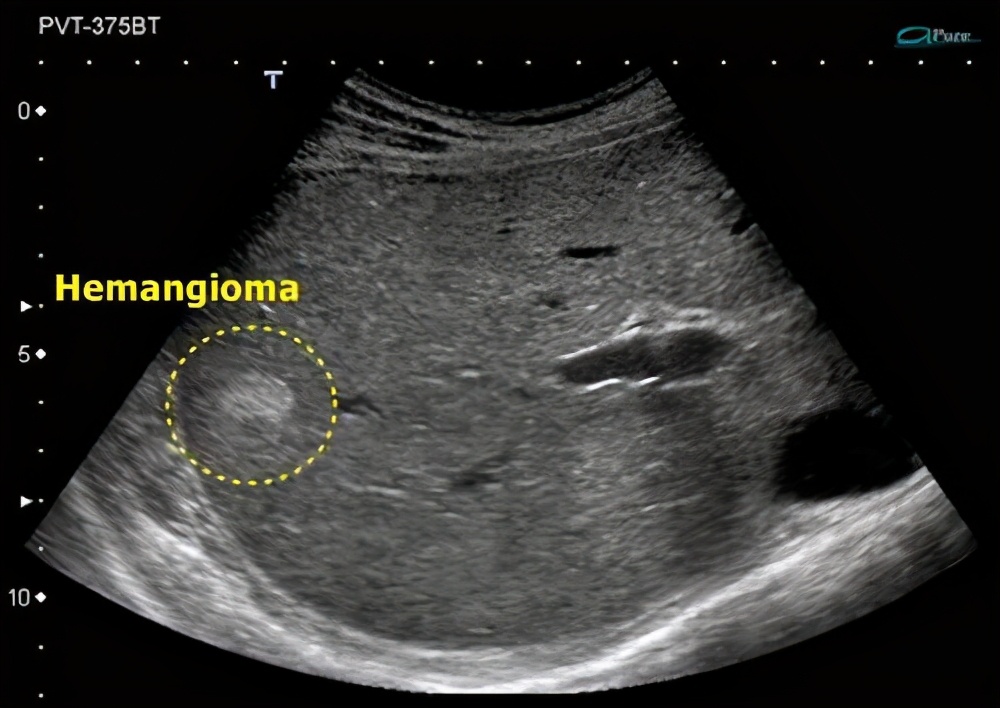

彩超

做超声检查的话,你会发现我们与肝脏周围组织边界是清楚的,互不干扰。我们内部的结构比较均匀,呈高的或强的回声肿块。但是,并非所有人的血管瘤都是高回声的,大约67%~79%的人是这样的。

少部分人可能会表现为低回声,这个多见于脂肪肝的患者,由于我们的周围肝实质通常有一些明亮的信号,干扰了超声的显示。

不过当我们的体积大于5厘米的时候,由于内部有血栓或者纤维化形成,可能会出现混合性的回声。

这里面有一点就要特别引起注意了,因为有一些恶性的疾病,比如说肝癌和肝转移性的肿瘤,如神经内分泌肝转移瘤或肺癌肝转移,他们的超声变化是相似的,需要做分辨率高的其他检查来诊断。